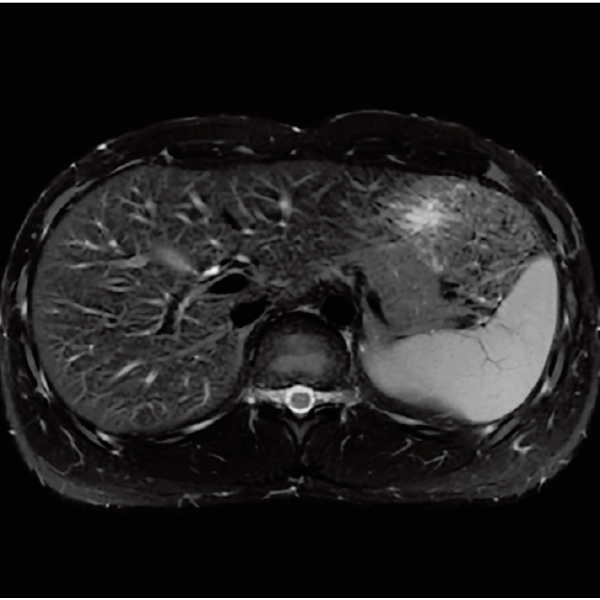

T1WI Dual Echo (Out) Breath hold

RADAR:Body movement suppression technology for those who cannot hold still

T2*WI RADAR, 2:34

T2WI FatSat Respiratory gating RADAR, 2:16